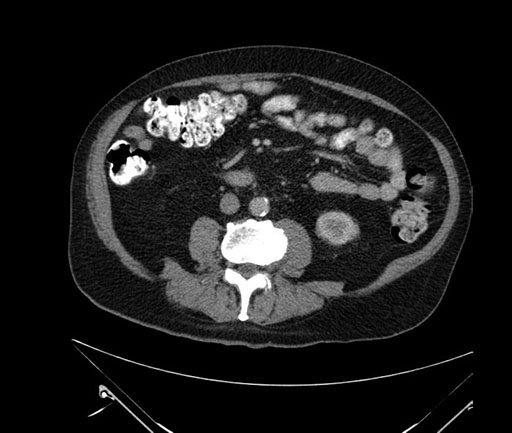

Whipple (pancreaticoduodenectomy) [case 7]

Imaging Analysis

Look through the patient's CT scan to identify any areas of concern for the necessary procedure.

Based on your CT findings, which issue(s) would give reason for "planned slowing down moment(s)" in this case?

Considering a standard Whipple procedure, what step(s) of the operation would you do differently in this case?